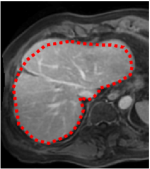

An example of CT/CBCT and MR/CBCT registration results are shown in figures 3 and 4, respectively. For both cases, the CBCT image (first column) was acquired intra-operatively after needle insertions and was employed as a reference for image registration. The pre-operative image is displayed before registration (second column), after PM-EA (third column) and after PM-EA+Evo (fourth column). The occurrence of patch shifts is reported for each spatial direction in panels (m–o): for each histogram, the shift with maximal occurrence is shown by the red dashed line. For panels (a–l), a ROI — manually defined on the CBCT image/encompassing the liver — is shown using red dash lines. Our visualization shows an improved correspondence of the contour of the liver with the manually defined liver boundary when the PM-EA solution is employed (see 3(c,g,k) and 4(c,g,k)). Moreover, an even better correspondence of the contour is observable using the PM-EA+Evo solution (see 3(d,h,l) and 4(d,h,l)).

Trans.

[X-Y]

CBCT

(a)

MRI / No registration

(b)

MRI / PM-EA

(c)

MRI / PM-EA+Evo

(d)

Sag.

[X-Z]

(e)

(f)

(g)

(h)

Cor.

[Y-Z]

(i)

(j)

(k)

(l)

(m)

(n)

(o)